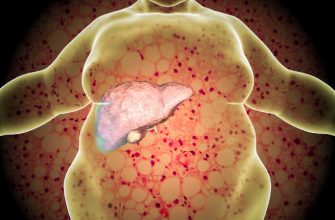

Liver disease is a condition that affects the liver’

Liver dysfunction, also known as liver disease, is